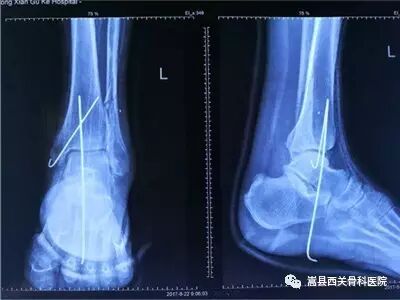

昨天下午我院手足显微外科成功完成一例轴型皮瓣切取移植术,据了解,患者是上山拾柴禾时突发晕厥跌落致伤左肘部、左膝部及左踝部,左肘部及左膝部皮肤擦伤,左膝部伤口出血,左踝关节向外后侧脱出,肌腱及骨质外露,踝关节功能障碍。

入院后急诊在手术室椎管内麻醉下行“1、左侧踝关节开放性脱位复位并踝关节稳定术 2、左侧足踝部扩创术并创伤负压膜吸引术 3、左侧胫前动脉断裂吻合术 4、左足拇长伸肌肌腱断裂修补术 5、左侧胫骨远端开放性骨折切开复位内固定术”,于术后第6天拆除负压引流膜见:创面清洁,无明显异常渗出,遂在硬膜外麻醉下行:“1、左侧踝部扩创术并带蒂轴型皮瓣切取移植术2、左侧下胫腓关节分离螺钉内固定术3、左下肢取皮植皮术4、左小腿供区创伤负压膜吸引术”。术后患者生命体征平稳,踝部皮瓣血循良好,张力适中。